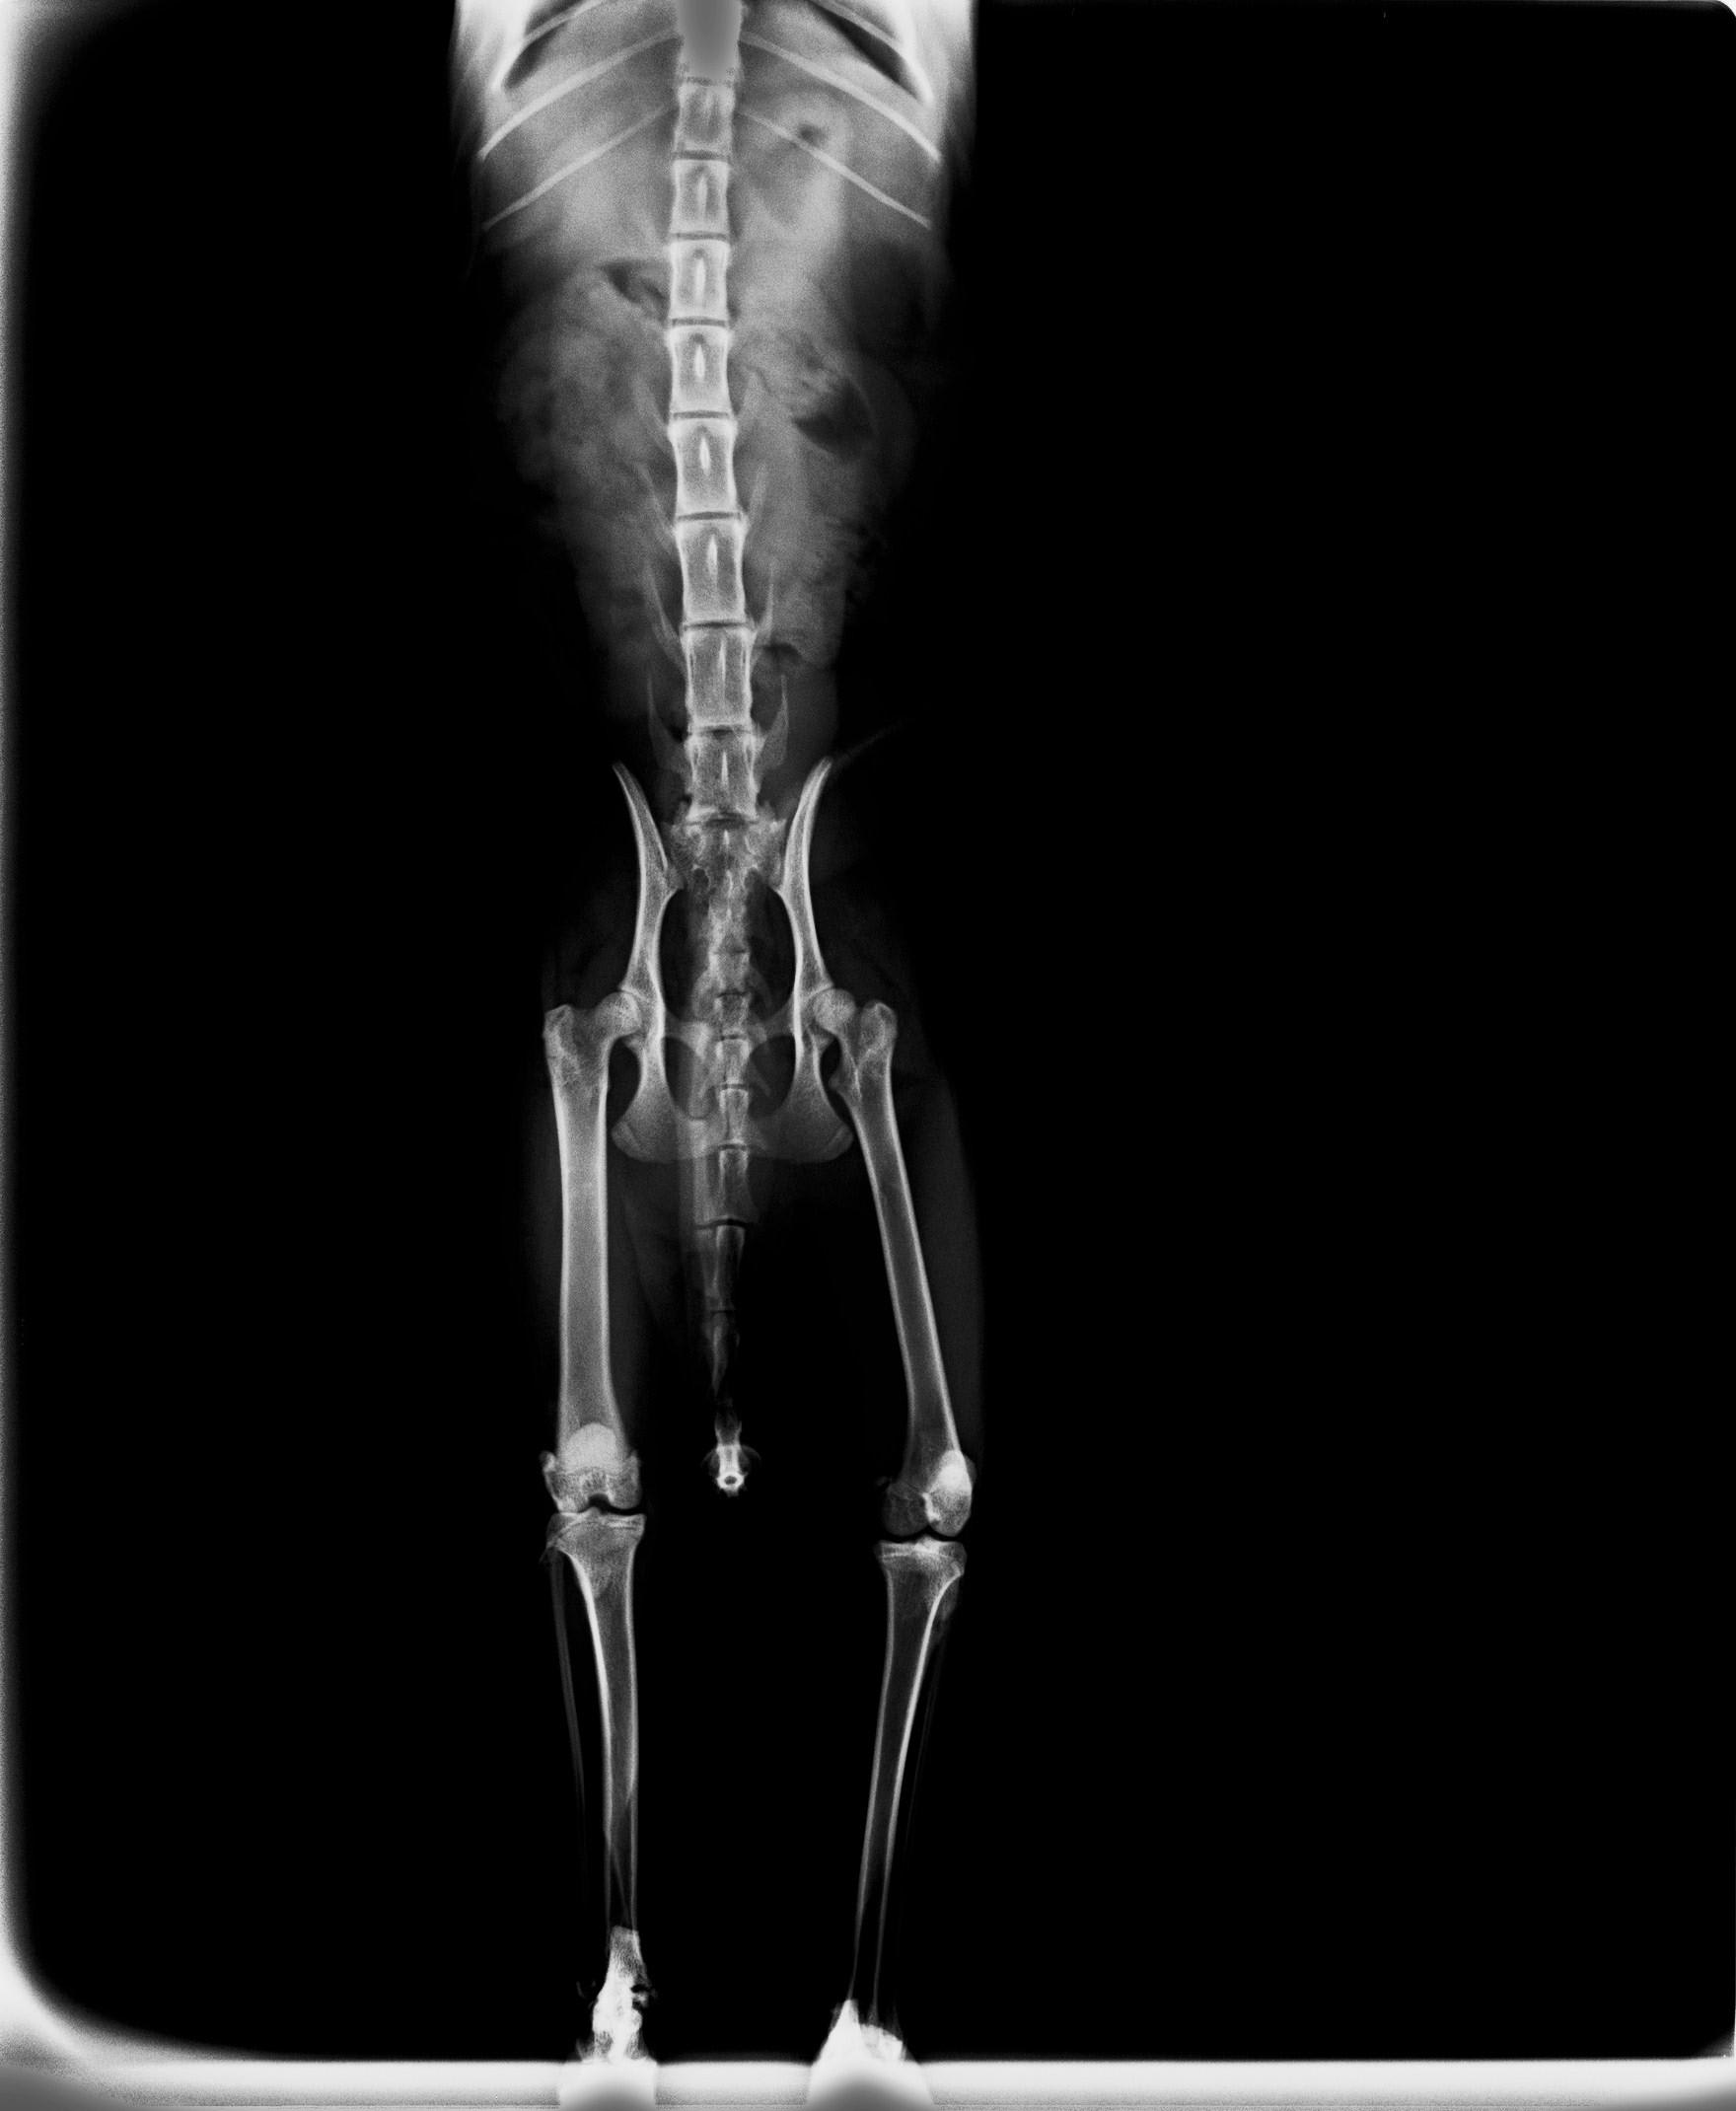

Hello, my cat (female, neutered, year and a half) had calicivirus. Now she limps and she can't jump to hight places. One vet says that she has osteoarthritis in the left elbow and right hip. He recommends growth factors and stem cells, not a surgical intervention.. The other veterinarian says that it is insufficient ossification because she is still too young. He recommends two weeks of calcium. These two oppinions are totally opposed. I don't know what to do. These are the x-rays. Thanks

You do not mention when she had the virus - this is commonly associated with severe lameness which resolves over time in most cases (there does also appear to be poor fusion or injury of one elbow). The xrays are very difficult to assess of the screen, especially as there are no markers to identify right from left limbs and the colour does not always reflect accuratley when transferred. They should not be diagnostic without comparing them to the full physical exam for muscle loss etc. A full review of her diet history would be worthwhile as poor kitten nutrition can lead to complications but generally it appears at an earlier age.